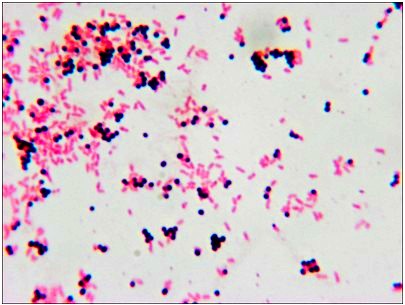

顯微鏡所拍圖片

上海野生動(dòng)物園是我國(guó)最大的國(guó)家級(jí)野生動(dòng)物園,占地153公頃,距市區(qū)35公里。上海野生動(dòng)物園匯集了世界各地具有代表性的珍稀動(dòng)物200余種上萬(wàn)余頭(只),其中有來(lái)自國(guó)外的長(zhǎng)頸鹿、斑馬、羚羊、犀牛等,也有我國(guó)的一級(jí)保護(hù)動(dòng)物:大熊貓、金絲猴、華南虎、亞洲象等。上海野生動(dòng)物園醫(yī)療診所購(gòu)置明美顯微鏡,主要用來(lái)判讀野生動(dòng)物感染何種病菌,以此對(duì)癥下藥,給動(dòng)物一個(gè)正確的治療。客戶還需要一套成像系統(tǒng),更方便診斷,交流??蛻艨吹牟【枰?00X油鏡。結(jié)合老師的預(yù)算情況,明美工程師給老師配置了一套性價(jià)比很高的數(shù)碼顯微鏡-ME21.配備了奧林巴斯的主機(jī),明美成像系統(tǒng)MD50。